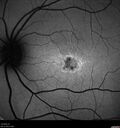

25 year old with Stargard and 2 ABCA4 mutations.vu 191 foisShe has worn glasses since she was a kid. Since she became an adult her vision started to deteriorate more rapidly. This seems to have been happening since she entered the accounting department for the last two years. Her vision is worse in the light especially when she is driving. She can see green lights in the night but not in the day. She sees better on a dark background than on a light background. Her mom is genetically visually impaired with Stargardts. Her father has RP. The mother was genetically tested in Boston about 23 years ago. That was when the gene was first being isolated. (The mother has seven brothers and sisters and four have stargardts and they are legally blind. Also one cousin has it.)

VA OD: Dcc20/160-1 PH20/80 Ncc20/200-2

VA OS: Dcc20/160-2 PH20/80-1 Ncc20/200-1

IOP: TP: OD:20 OS:21